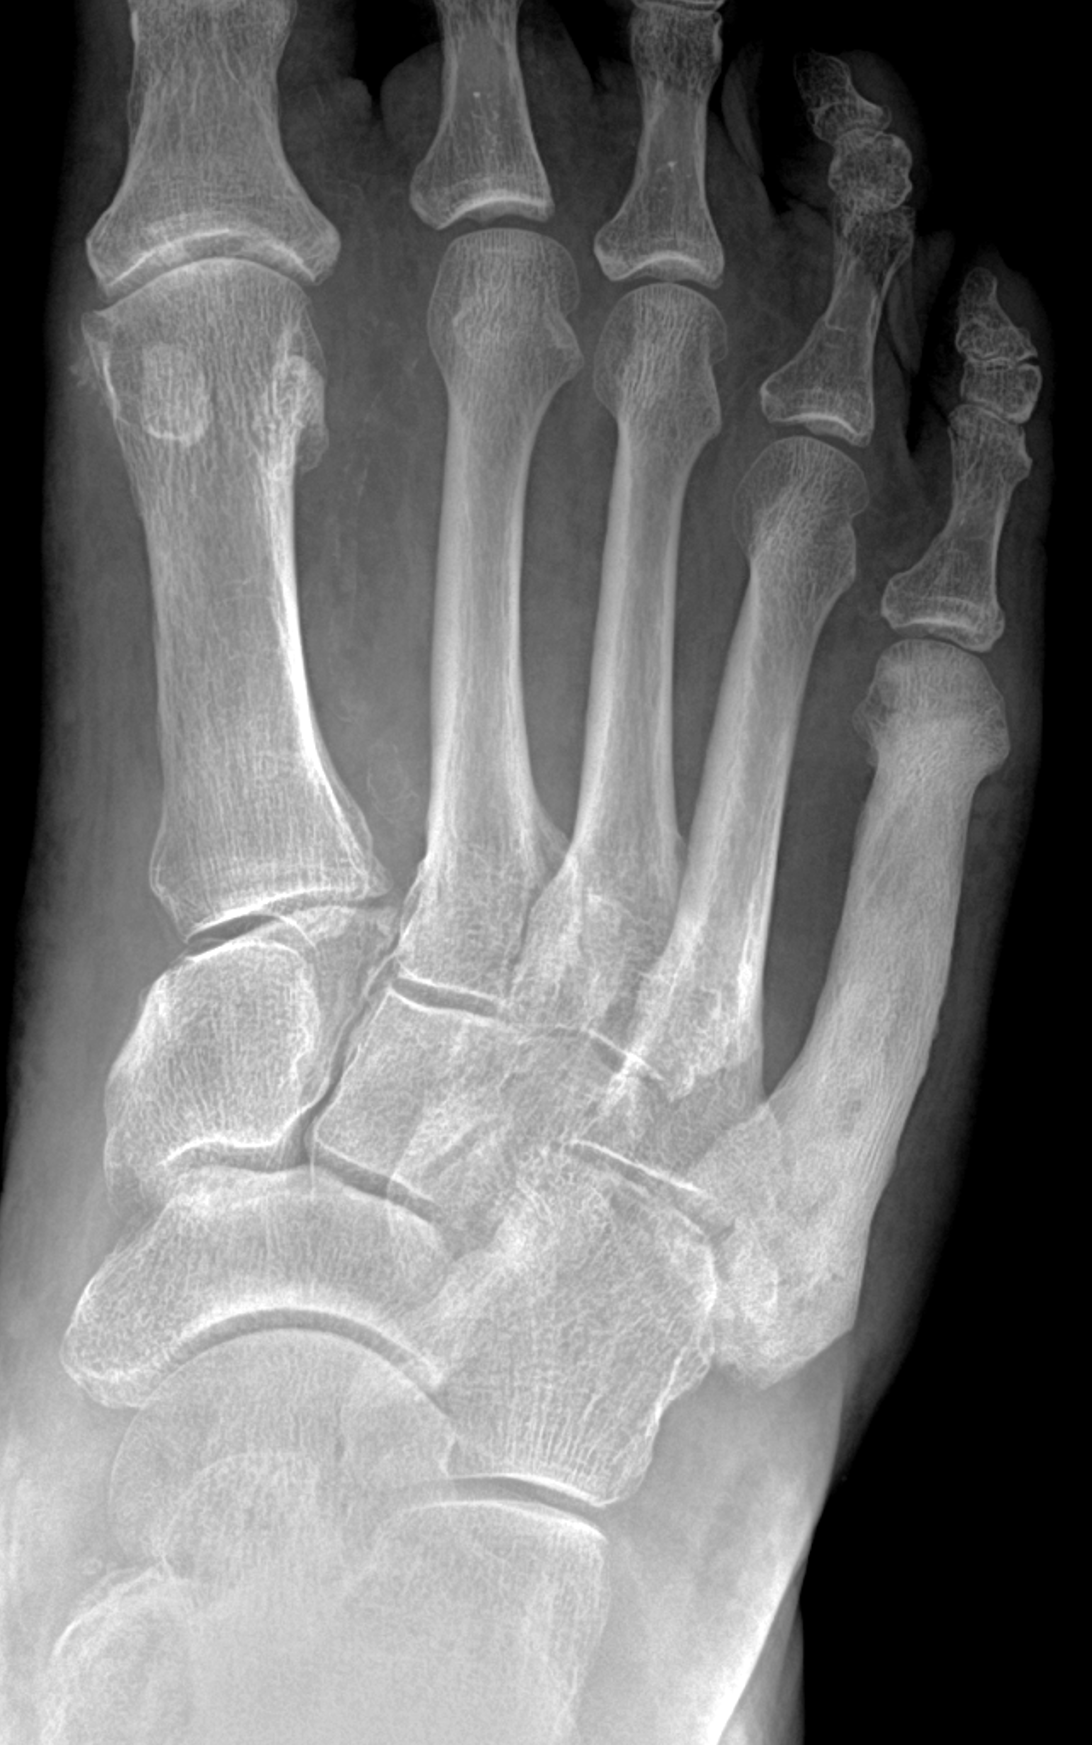

Figure 2: (2A) Sagittal T1-weighted image shows severe thickening of the distal femoral cortex (yellow arrow) and thickening and coarsening of the trabeculae in the femoral condyles (red arrow). Note the high signal intensity fatty marrow in both regions. (2B) Axial fat-suppressed, fluid sensitive sequence through the distal femoral shaft shows severe thickening of the bone cortex, with small round and tubular high-signal intensity foci within the cortex (arrow), likely representing cysts and dilated vascular spaces. (2C) Axial fat-suppressed, fluid sensitive sequence through the femoral epicondyles shows heterogeneous marrow (asterisks), with areas of suppressed marrow fat, mildly increased marrow signal intensity, and small cyst-like lesions. (2D) AP radiograph shows typical findings of mixed phase Paget disease in the distal femur including cortical thickening, course trabeculae, and bone enlargement. Secondary medial compartment predominant osteoarthritis has developed, likely contributing to symptoms.

Figure 9: Sclerotic phase Paget disease of the fifth metatarsal, MRI pattern 3. (9A) Sagittal T1-weighted image shows nearly uniform hypointense marrow in the fifth metatarsal, with small islands of preserved marrow fat (arrows), which helps exclude a malignant process. (9B) Sagittal fat-suppressed T2-weighted image shows mildly increased signal intensity throughout the marrow (asterisk). (9C) Dorsoplantar radiograph demonstrates sclerosis throughout the fifth metatarsal, due to cortical and trabecular thickening. Note the bone enlargement and bowing. (9D) Short-axis CT image shows nearly uniform sclerosis throughout the fifth metatarsal.